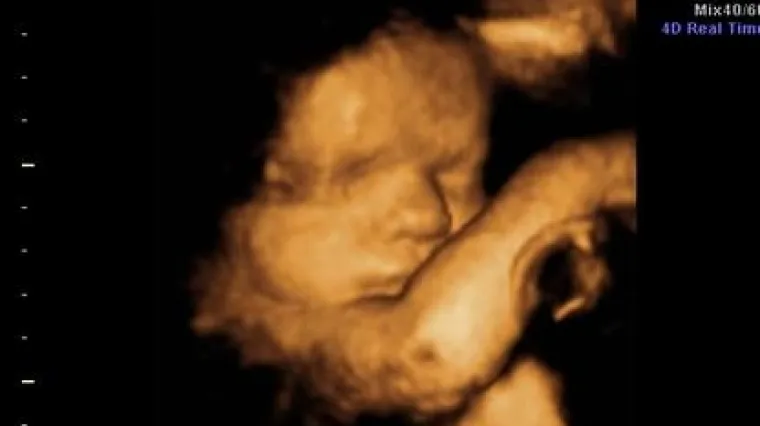

Tko abortira dobit će otkaz

Vlasnik jedne ruske tvrtke izjavio kako će dati otkaz svim radnicama koje se odluče abortirati.

Ruski proizvođač mlijeka Moloko najavio je da će dati otkaz svim radnicima koji žive u izvanbračnim zajednicama, kao i radnicama koje su abortirale.

"Abortus je ubojstvo. Ne želim raditi s ubojicama", izjavio je vlasnik te vlasnik Vasily Boiko-Veliki u intervjuu za radio Eho Moskvi. Onim radnicima koji žive sa svojim partnerima, a nisu vjenčani, Boiko je dao rok do 14. listopada da to učine. U suprotnom, slijedi otkaz.